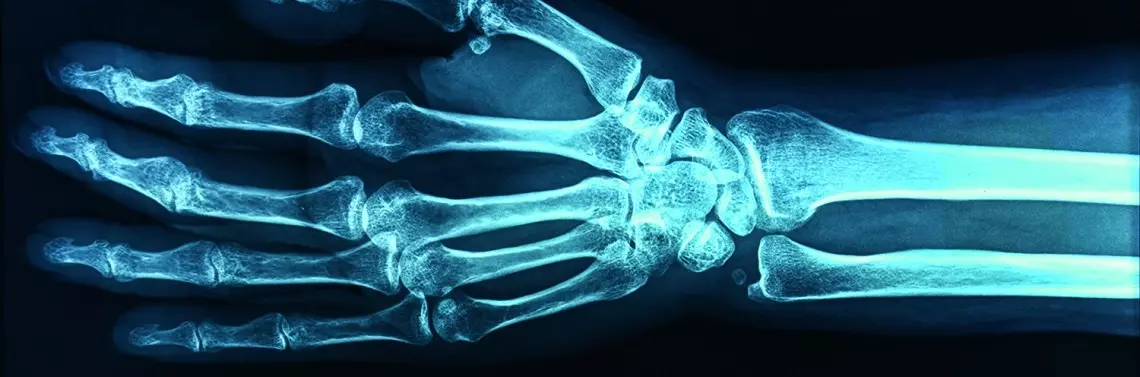

Fizjoterapia urazów stawu nadgarstkowego u narciarzy i snowboardzistów

Popularne obecnie narciarstwo i jazda na snowboardzie wiążą się z niebezpieczeństwem upadku, a co za tym idzie − ryzykiem powstania urazu stawu nadgarstkowego. Niestety wiele uszkodzeń nadgarstka jest nieprawidłowo rozpoznanych bądź nierozpoznanych, a tym samym niewłaściwie leczonych. Ogromne znaczenie dla odzyskania pełnej sprawności ręki, która uległa urazowi, ma postępowanie rehabilitacyjne.

W  obecnych czasach najpopularniejszymi sportami zimowymi są narciarstwo zjazdowe oraz snowboard uprawiane przez dzieci, młodzież oraz dorosłych. Obie te dyscypliny są uprawiane wyłącznie sezonowo w okresie zimowym i przez to większość osób, zakładając narty lub deskę snowboardową na nogi, nie jest odpowiednio przygotowana do sezonu. Sezon zimowy powinien być poprzedzony odpowiednim przygotowaniem motorycznym, tak aby zminimalizować ryzyko wystąpienia kontuzji. Wiele osób w ciągu całego roku nie ma styczności z innym sportem lub jest to rzadki kontakt, co ma znaczny wpływ na poziom przygotowania do sezonu zimowego. Statystycznie urazów snowboardowych jest dwukrotnie więcej niż urazów narciarskich. Jedną z przyczyn jest większa częstotliwość upadków snowboardzistów w porównaniu z narciarzami. Drugą przyczyną takiej dysproporcji jest rodzaj urazów w obu dyscyplinach i moment udzielenia pomocy medycznej. Urazy u snowboardzistów to najczęściej urazy kończyn górnych (nadgarstków), gdzie pomoc udzielana jest na stoku. U narciarzy najczęstsze są urazy skrętne, które często nie są rozpoznawane w momencie urazu i diagnoza stawiana jest wiele tygodni lub miesięcy po urazie jako dolegliwości o nieznanej przyczynie. W przypadku snowboardzistów statystyki mówią o 3−6 zdarzeń na każde tysiąc dni uprawiania dyscypliny. Przeciętny snowboardzista doznaje jednego urazu na każde 190 dni jazdy. Biorąc pod uwagę sezonowość dyscypliny, jeżeli jedna osoba jeździ dwa tygodnie w roku, to według statystyk 1 na 16 lat dozna urazu. Statystyka więc nie wygląda źle, ale jeżeli weźmie się pod uwagę 95 tys. złamań w obrębie nadgarstka w sezonie na świecie, to wygląda to znacznie poważniej. Urazy nadgarstków wśród snowboardzistów stanowią 25% wszystkich kontuzji, w dalszej kolejności są urazy głowy, barków, łokci, a na samym końcu kończyn dolnych. Jeżeli porówna się urazy, które przytrafiają się narciarzom, to problem jest odwrotny. U narciarzy najczęściej występującymi urazami są urazy stawów kolanowych. Na drugim miejscu są urazy kończyn górnych, a w dal...